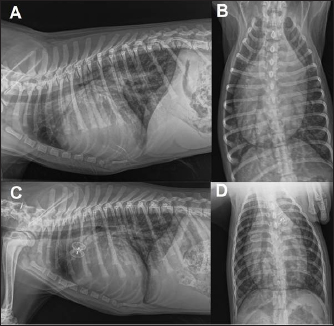

Fig. 5. Dual mode transthoracic echocardiography (right parasternal short axis view, optimized for duct visualization) 24 hours after surgery. The device discs (arrows) are correctly positioned and there is no evidence of residual shunt or pulmonary arterial obstruction given the laminar flow in the right pulmonary artery on CFM Doppler.

Echocardiographic checks at 3 and 24 hours showed complete PDA closure, correct positioning of the mVSDO (Fig. 5), and a clear reduction in left heart volume overload (LA: Ao decreased from 1.72 to 1.3, LVIDDN decreased from 2.49 to 2.43).

The dog was then discharged and a check-up was scheduled at 3 months. The 3-month echocardiographic examination confirmed complete occlusion of the PDA with the absence of residual shunting, correct positioning of the device, disappearance of mild mitral regurgitation, and reverse remodeling of the cardiac chambers (kg 11.9, BSA 0.54, LA:Ao 1.14, LVIDDN: 1.94).